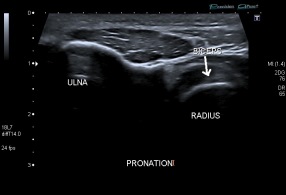

Nous passons donc par voie postérieure, l'avant bras étant positionné en pronation. L'aiguille peut être entrée n'importe où et son trajet sera suivi sur l'écran jusqu'à la cible, les seules structures à franchir étant alors la peau et un plan musculaire.

A noter que la proximité du nerf interosseux postérieur entraine, si l'on injecte de la xylocaïne, une sensation d'hypoesthésie limitée à une partie du territoire d'innervation du nerf radial à la main, et une parésie des extenseurs du poignet et des doigts.